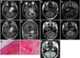

Slow-growing intracranial tumor

An ependymoma is a tumor that arises from the ependyma, a tissue of the central nervous system. Usually, in pediatric cases the location is intracranial, while in adults it is spinal. [Source: Wikipedia ]